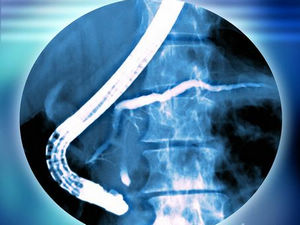

2012 EAES临床实践指南:腹腔镜胆囊切除术中胆管损伤的预防和治疗

Prevention and treatment of bile duct injuries during laparoscopic cholecystectomy: the clinical practice guidelines of the European Association for Endoscopic Surgery (EAES).

2012年10月6日,欧洲内镜外科协会(EAES)在线公布了腹腔镜胆囊切除术中胆管损伤的预防和治疗指南。